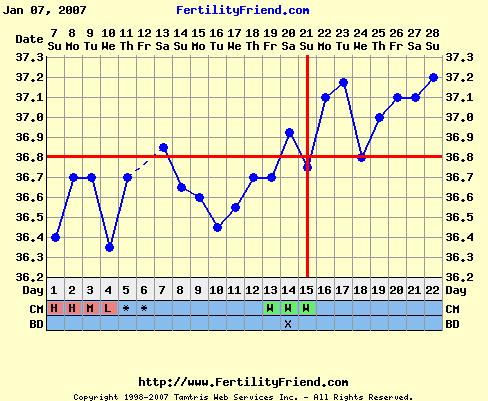

De azért közlöm veletek a hőgörbém, egy PCOStól nem is rossz!

Nagyon tetszik